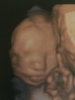

Basia Twoja Ślicznotka jest przeurocza <3 Uwielbiam zdjęcia 3d, tak pieknie widać take niewinne dzieciątko <3